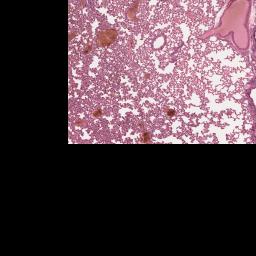

Index of /PathCampVirtualSlides/lung_post-mortem_clot/3